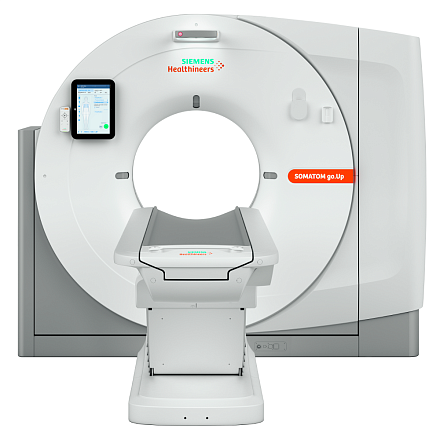

Siemens SOMATOM go.Up компьютерный томограф

SOMATOM go.Up - компьютерный томограф для проведения рутинных и целевых осмотров, лучевой терапии и ангиографии. Система отличается инновационным дизайном рабочего места и полностью обновлённой концепцией сервиса, которая способствует снижению расходов по эксплуатации. Подходит для обследования головного мозга, легких, толстой кишки, сердца, сосудов. Вы можете заказать или купить со склада в наличии компьютерный томограф Siemens SOMATOM go.Up по выгодной цене, от надежного официального дистрибьютора "МСТ", с бесплатной доставкой в любой город по всей России.

SOMATOM go.Up позволяет расширять клинический диапазон и развиваться, достигая существенных результатов. Благодаря использованию высоких технологий система обеспечивает результаты, которые ранее были доступны только на томографах высокого класса. Кроме того, SOMATOM go.Up хорошо подходит для целей лучевой терапии. Благодаря пакету RT Image Suite, установленном на рабочей станции сбора данных, можно без труда выполнять разметку, оценивать изображения и проводить оконтуривание мишеней для лучевой терапии.

Позволяет выполнять сканирование с низкой лучевой нагрузкой, что очень важно для оптимальной заботы о пациенте. SOMATOM go.Up выполняет сканирование больших диапазонов за одну задержку дыхания с высоким пространственным разрешением.

SOMATOM go.Up позволяет проводить высококачественные ангиографические исследования сосудов с хорошим контрастным усилением, субмиллиметровыми срезами и точной синхронизацией по времени.

SOMATOM go.Up оптимизирует качество изображений и снижает лучевую нагрузку в рутинных неврологических исследованиях. SOMATOM go.Up отличается высокой скоростью сканирования и высоким качеством полученных изображений, что повышает качество диагностики особенно мелких сосудистых структур.

SOMATOM go.Up позволяет проводить скрининговые исследования лёгких и толстой кишки, а также исследования сердца для оценки коронарного кальция. Благодаря субмиллиметровой коллимации SOMATOM go.Up обеспечивает высокое пространственное разрешение, тем самым повышая чувствительность диагностики в онкологии.